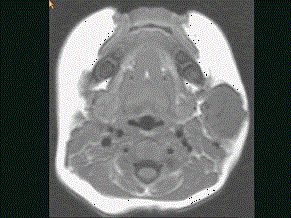

问题 40岁,患者,左面部渐进性增大的包块,MRI检查如图所示,应考虑为 ( )

选项 A、左面部脂肪瘤 B、左面部神经纤维瘤 C、左面部囊肿 D、左面部脓肿 E、左面部毛细血管瘤

答案 E